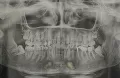

Мне 28 лет. У меня начал пробиваться зуб мудрости в верхнем ряду. Он уже прощупывается, но еще не пробился. И я обнаружила, что растет он криво, в щеку. Сместился и растет не посередине десны, как все зубы, а в сторону щеки. Понимаю, что чем больше он будет прорастать, тем больше вредить щеке и в итоге придется удалить его.

Можно ли изменить направление роста сейчас, на этапе, пока он еще не пробился?

Естественно нет, к тому же, при росте, данный зуб сместит весь зубной ряд и впоследствии вам потребуется ортодонтическая помощь. Данный зуб необходимо удалить еще в зачатке.